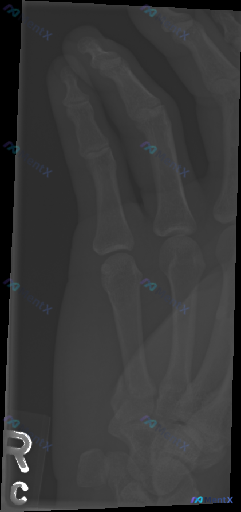

这份是右手指斜位X光片,影像科报告的描述是:

- 各段骨皮质连续,未见明显骨折线或脱位征象

- 关节对位正常,关节间隙清晰

- 骨质密度均匀,未见骨侵蚀或增生

- 软组织轮廓自然,未见明显高密度异物

- 总结:本次检查未见明显骨折、脱位或骨质破坏征象